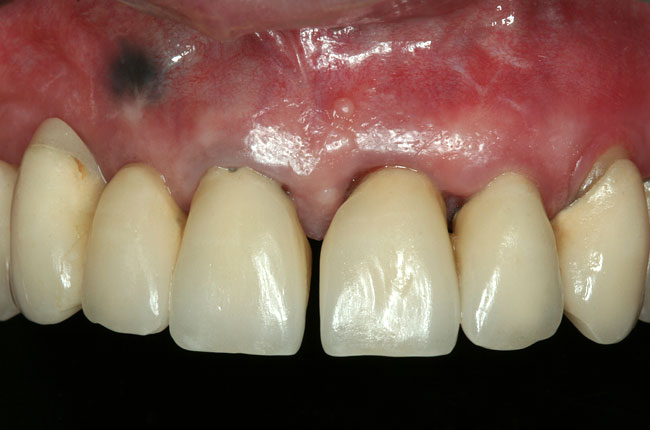

Abbildungen 3-5: Die klinischen Fotographien zeigen den Zustand nach der ersten professionellen Zahnreinigung.

Der komplexe Fall Der komplexe Fall

Abb. 5

Abb. 6